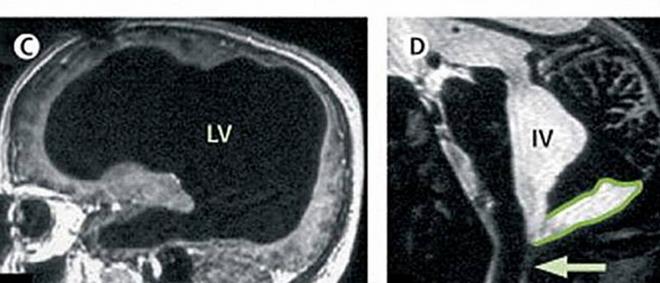

英国《镜报》报导,一名44岁的法国男子,日前因脚伤入院治疗,医生却在检查过程中意外发现,他竟然只剩半边脑袋!而且神奇的是,虽然他只剩下半颗脑,生活却几乎没受到影响。

进一步追踪发现,原来这名男子年幼时曾罹患脑积水,医生当时以分流管排除积水,直到14岁才移走,却没料到其实积水的问题并没有根治。这些积水长久以来造成了该男子脑中的物质逐渐被分解,最后竟丧失了50%至75%的脑面积物质。

该案例的研究员里昂内尔(Lionel Feuillet)表示,这名男子的左右脑皆有缩小,这些区域负责控制动作、情感、语言等功能,照理说应该会严重影响他的生活,不过该男却仍能正常过日子。里昂内尔推估,这是因为脑内能自行重组,让大脑其他尚未受损的区域负责原先的工作。